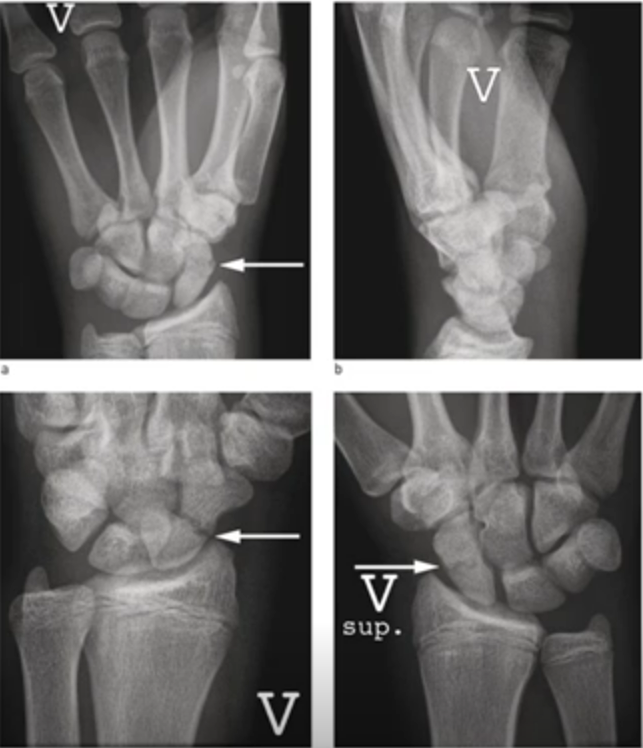

Scaphoid Fractures:

Scaphoid Fractures

- 4 xray views: